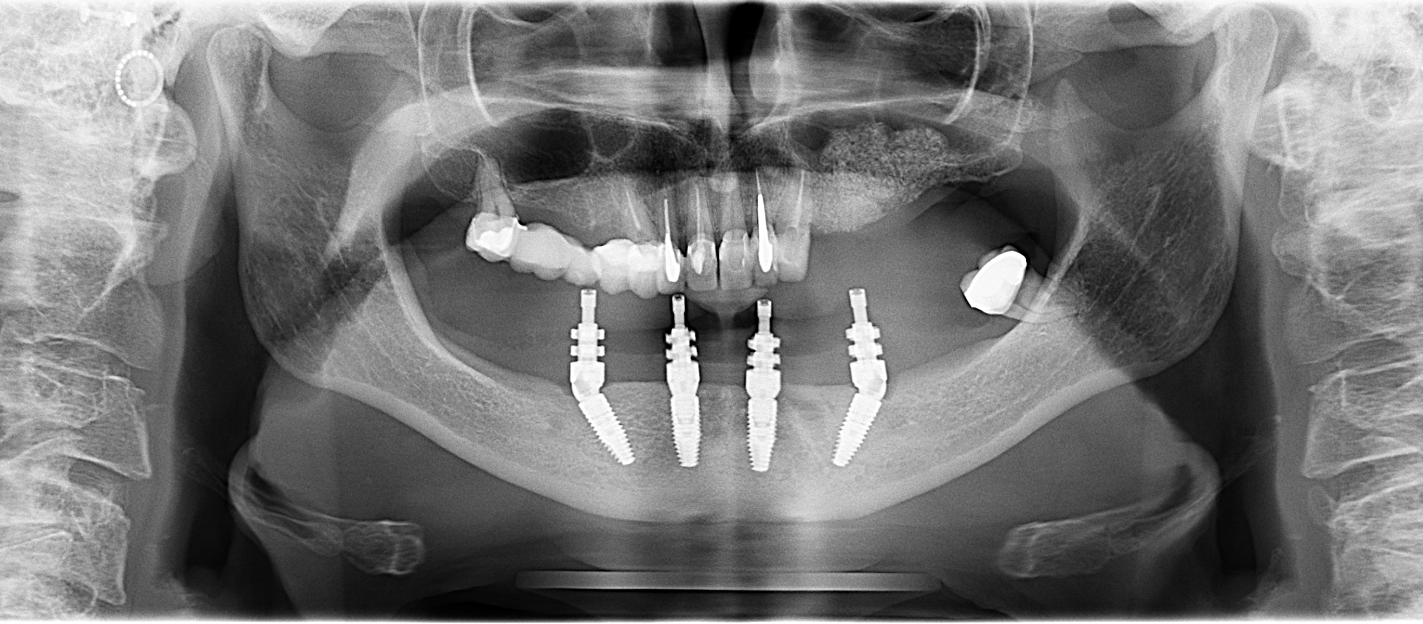

Az All-on-4 technika során négy darab implantátum kerül beültetésre az állcsontba, amelyeken majd egy ún. körhíd (összes fogat pótló rögzített fogpótlás) rögzül. A két elülső implantátum egyenesen, míg a két hátsó implantátum ferdén kerül behelyezésre.

Az implantátumok elhelyezkedése

Az All-on-4 különlegessége az implantátumok elhelyezésében rejlik:

- két implantátum az állcsontok elülső részén

- két implantátum döntött szögben a hátsó területen

Mivel a hátsó implantátumok döntött szögben helyezkednek el, így sok esetben elkerülhető a csontpótlás, ami a leggyakrabban a hátsó területeken válik szükségessé.

- CBCT (3D CT) felvétel készítése

- az implantátumok típusa és elhelyezkedése

A műtét során négy implantátum kerül az állcsontba. Ez történhet akár azonnali implantációval is, azaz rögtön az eltávolított fogak helyére.

Idönként sebészi sablont alkalmazunk, amelyet előtte digitális megtervezünk ezáltal pontosan az előre megtervezett pozícióba kerülhetnek be az implantátumok. Ez például olyan esetekben fontos, ahol nagyon kevés a rendelkezésre álló csontállomány.